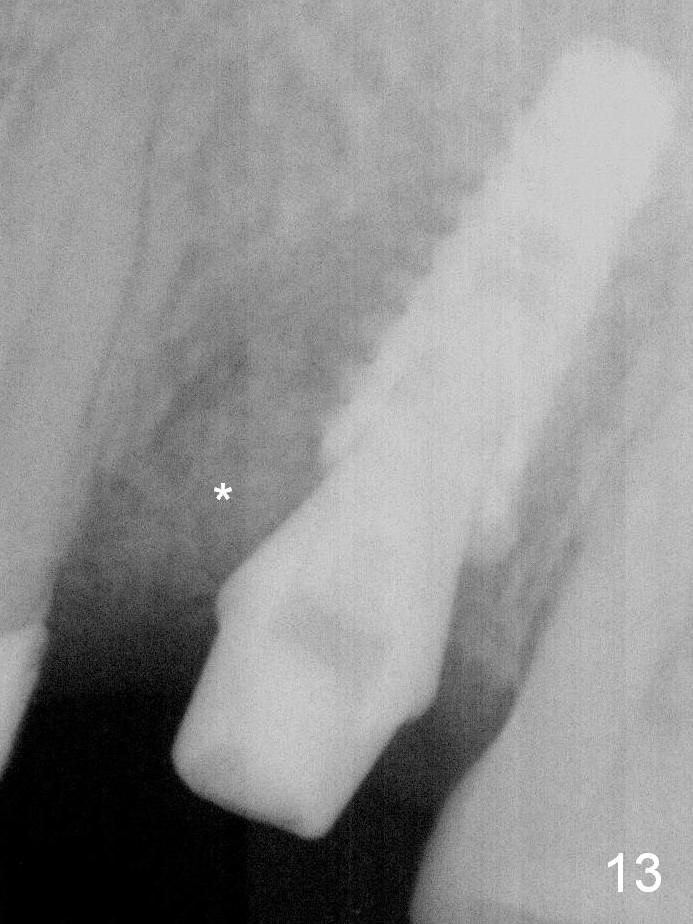

It seems that the provisional traps food. The former has been removed by the patient by the time she returns 3.5 months postop. The gingiva around the implant is healthy. The organization of the bone graft has changed (Fig.13, as compared to Fig.8,9). The implant has osteointegrated.